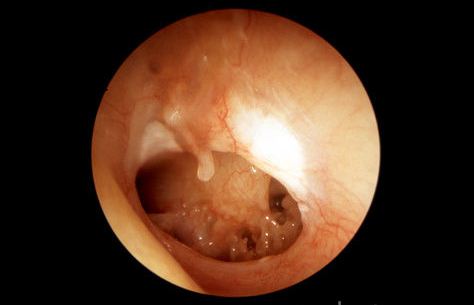

کلستئاتوم:

رشد غیر طبیعی پوست بداخل گوش میانی پشت پرده گوش،کلستئاتوم (cholesteatoma) نامیده می شود. عفونتهای مکرر و/یا پارگی یا کشیده شدن پرده گوش به سمت داخل می تواند موجب این حالت شود.کلستئاتوم اغلب بصورت کیست یا کیسه ای است که لایه های پوست قدیمی از آن می ریزد و این لایه ها در داخل گوش میانی باقی می مانند.بتدریج ،اندازه کلستئاتوم بزرگتر می شود و موجب تخریب استخوانهای ظریف اطرافش در گوش میانی میشود که باعث کاهش شنوایی می شود که با جراحی قابل اصلاح است.کاهش شنوایی دائمی،سرگیجه و فلج عضلات صورت نادر هستند ولی در صورت ادامه رشد کلستئاتوم ممکن می باشند.